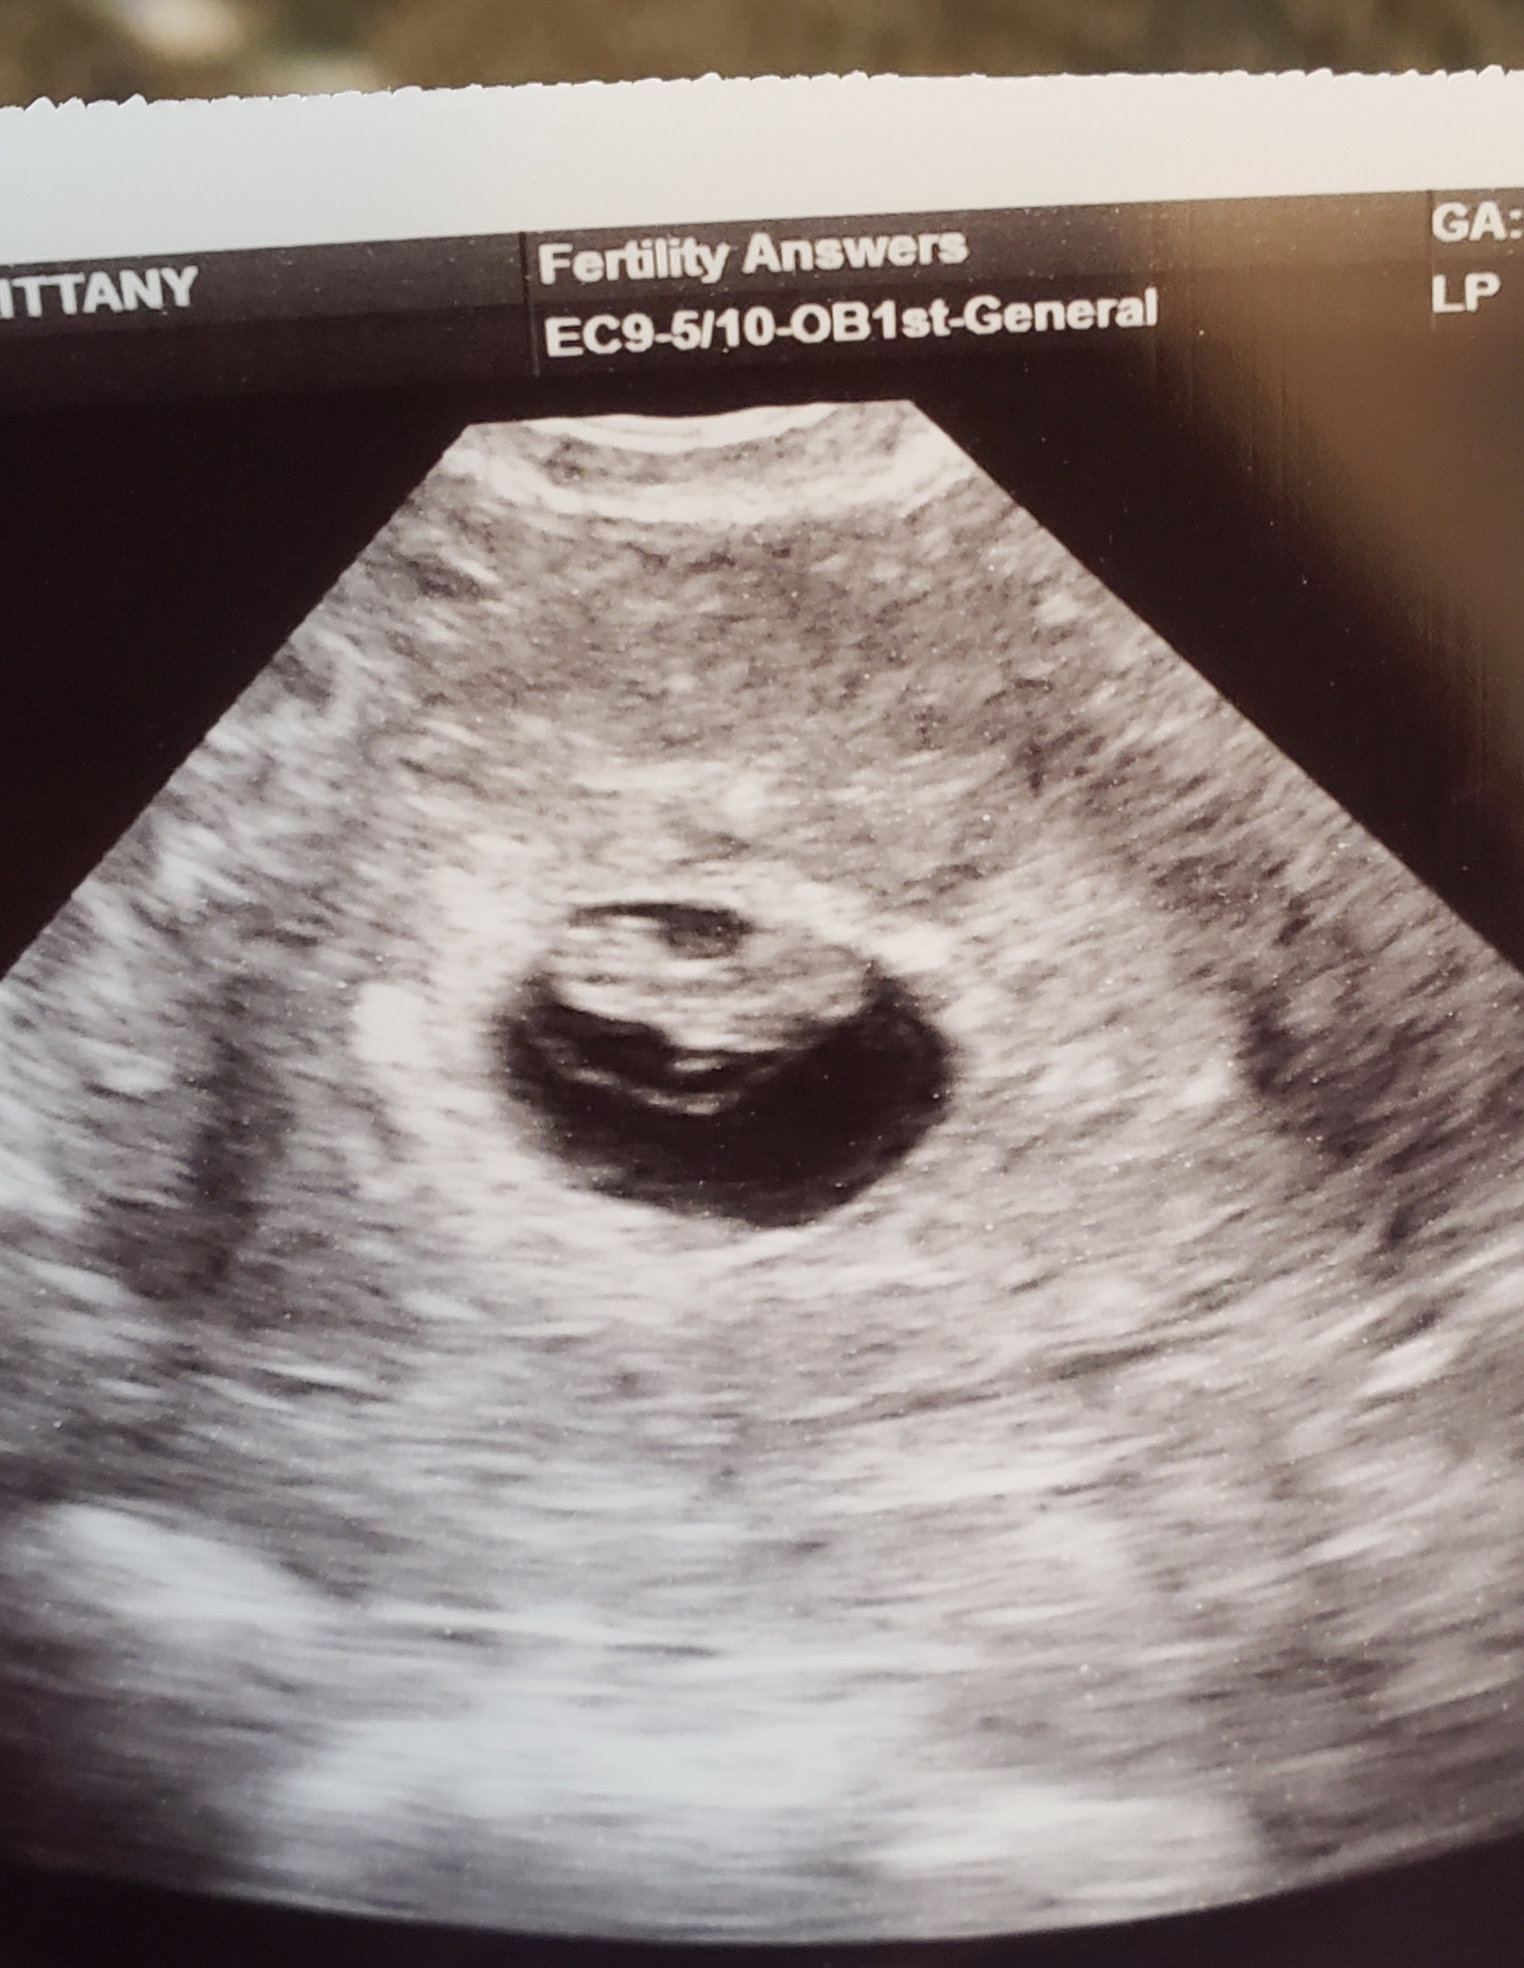

Went and saw baby again today, and learned that I am actually 10weeks1day not 9weeks4days. They are keeping my original due date since baby is growing. Next appointment will be with my OB to do the DNA testing